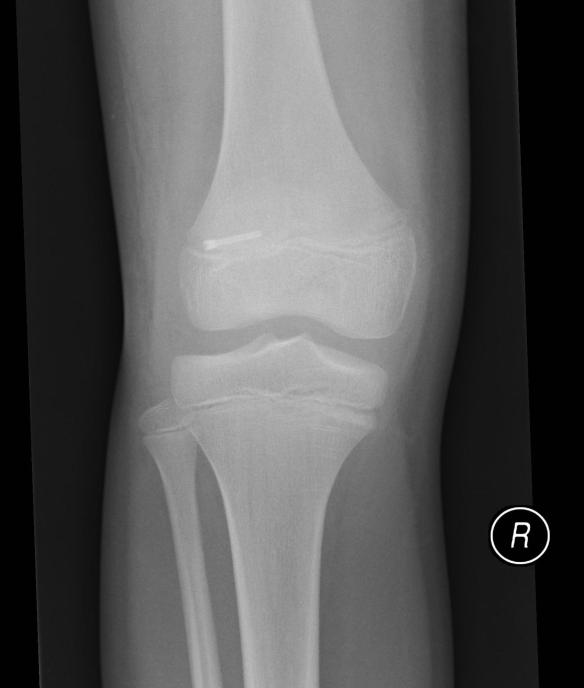

X-ray shows good progress, so time for a new cast and another 4 weeks on crutches.